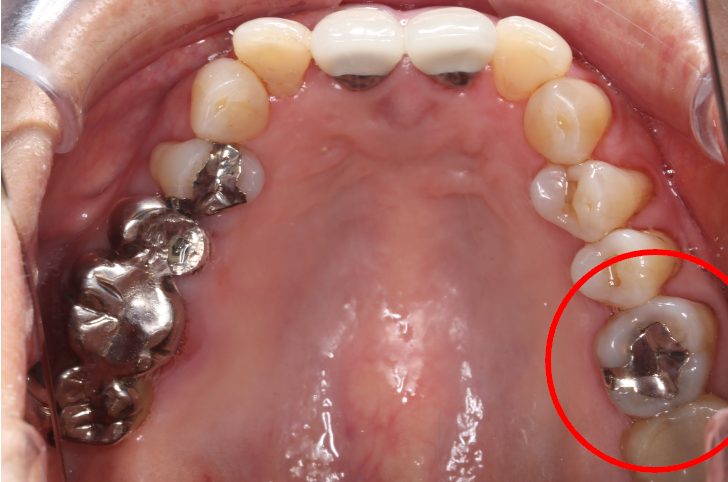

セラミック症例⑤

年齢50代女性

治療回数4回

治療内容セラミックインレー、クラウン

治療箇所

右下4番、5番、6番、7番 右上6番

治療費用500,000円